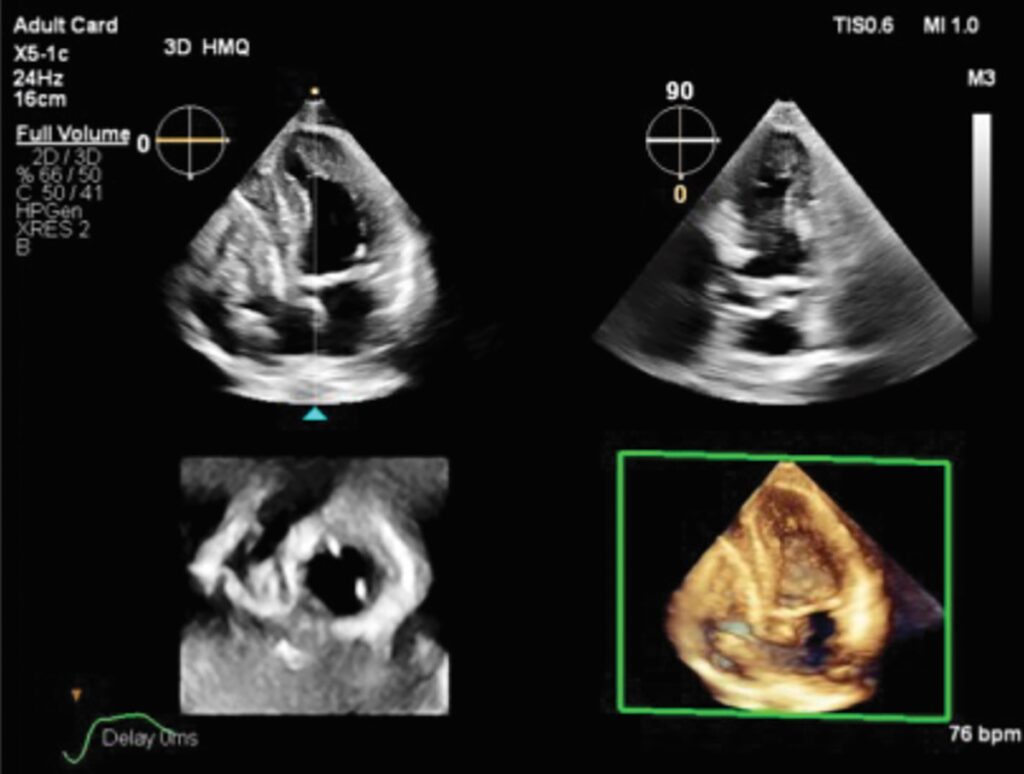

Transcend Plus visibly improves sharpness, contrast, and detail in 2D and 3D imaging, featuring the latest FDA-cleared enhancements for EPIQ CVx and Affiniti CVx, the release states. These upgrades support superior visualization of cardiac anatomy and function, enabling diagnostic confidence even in the most complex or technically challenging cases. The update also introduces the new 2D Auto EF Advanced feature, expanding AI capabilities for contrast images – essential for accurately assessing cardiac function.